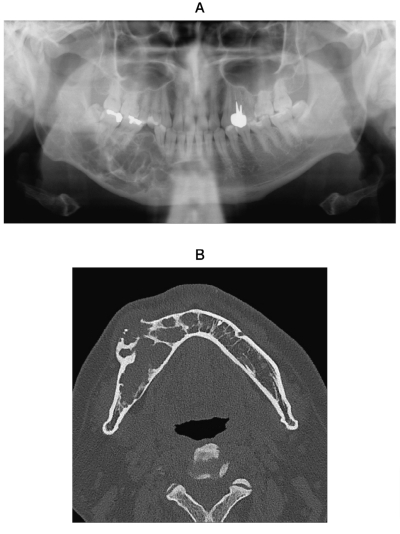

42歳の男性。下顎右側大臼歯の動揺を主訴として来院した。3年前から同部の歯肉の腫脹に気付き、徐々に歯が動揺するようになったという。初診時のエックス線画像、CT及び生検時の H-E 染色病理組織像を別に示す。